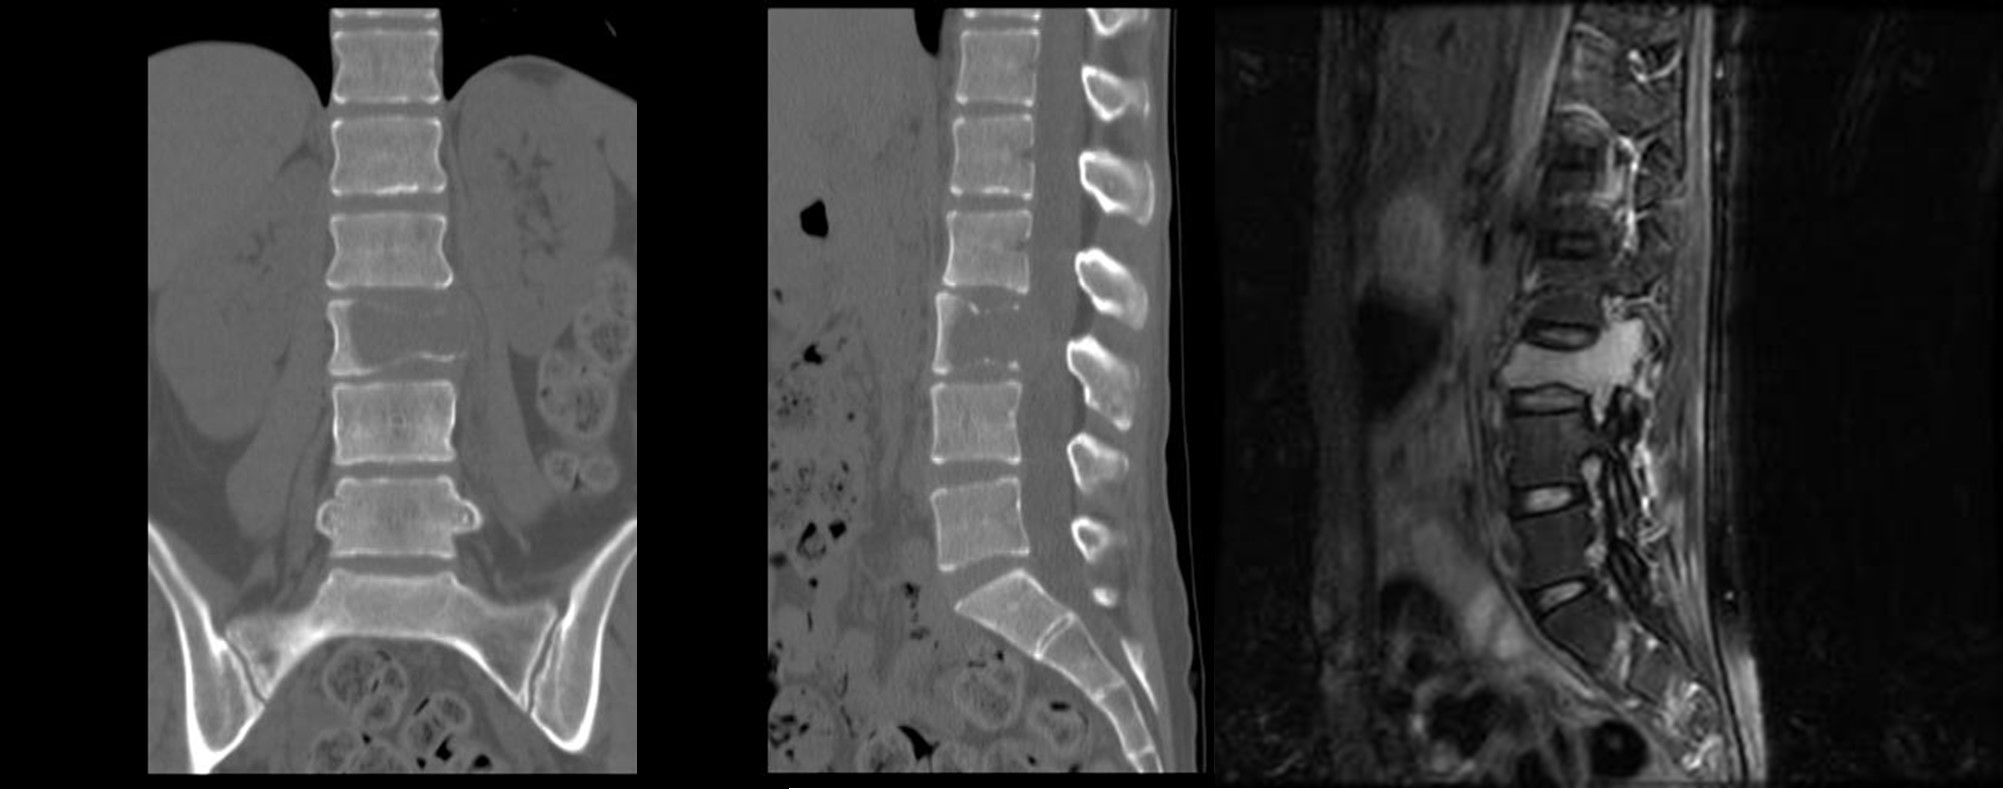

図 原発性(一次性)脊椎腫瘍

(左、まん中)矢印で骨が腫瘍で欠損している。

(右)矢印の白い部分が腫瘍